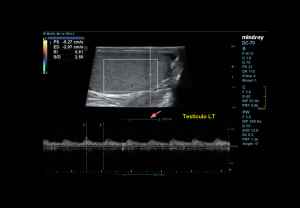

DOPPLER EVALUATION

Assessment of testicular perfusion is a critical component in acute scrotal pain.

Technical optimization:

- Use the lowest velocity scale and low wall filter to detect slow flow.

- Maximise colour gain for sensitivity, avoiding excessive noise.

Flow characteristics:

- Intratesticular arteries: Low-resistance waveform with continuous diastolic flow; peak velocities 3–5 cm/s; RI 0.4–0.7.

- Cremasteric and deferential arteries: High-resistance patterns.

- Veins: Non-pulsatile, low-velocity continuous flow.

- Centripetal and transmediastinal arteries: Low-resistance patterns.